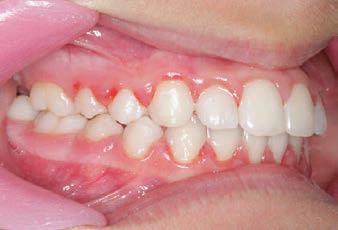

Carriere Motion 3D Appliance

Fastrack your orthodontic treatments. Save 6 months or more.

The SAGITTAL FIRST™ Philosophy is a time-tested approach that standardises, simplifies, and shortens Class II and Class III treatment times. It employs the Carriere Motion 3D Appliance to treat the AP dimension at the beginning of treatment before placing brackets or aligners. By resolving the most difficult part of treatment first, you can achieve a Class I platform in 3 to 6 months, shortening total treatment time by a minimum of 6 months1. You know how excited patients and parents become when you mention shorter treatment times.

CLASS II DIV.1 - Marra

PROVIDED BY: DR. LUIS CARRIÈRE

INITIAL - 4/4/18

PROGRESS 1 - 26/9/18 - Class I platform accomplished in 5.75 months with Motion 3D COLOR Appliance

PROGRESS 2 - 26/9/18 - Placement of the SLX 3D Clear Brackets

[CONTINUED ON NEXT PAGE]

with M-ONE .015 Cu Nitanium 27°

PROVIDED BY: DR. LUIS

PROGRESS 3 - 30/10/18 - With M-TWO .020 x .020 Cu Nitanium 35° archwire

PROGRESS 4 - 27/11/18 - 3 links power chain: 5, 4, bypass 3 to crimp hooks

PROGRESS 5 - 13/3/19 - With M-TWO .020 x .020 Cu Nitanium 35° archwire

PROGRESS 6 - 1/8/19 - With M-THREE.019 x .025 Beta Titanium wire

52 HENRY SCHEIN ORTHODONTICS

FINAL - 10/10/19 - Appliances removed AFTER

PROGRESS 7 - 10/10/19 - Final day in SLX 3D Clear Brackets BEFORE